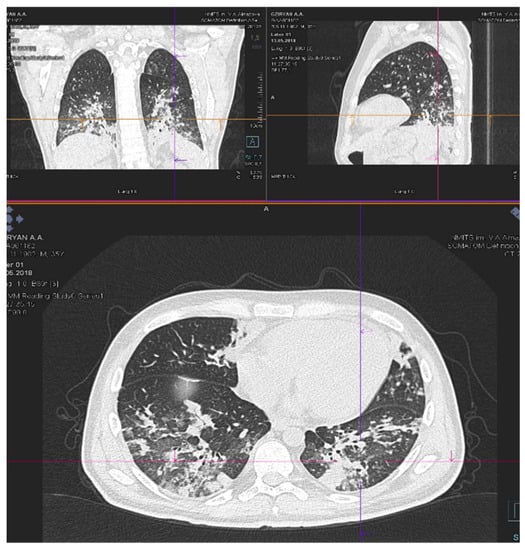

| Patient status before GO therapy initiation | The WHO performance status of 3. Marrow blast cells 88.6%, peripheral blood blast cells 60%, pancytopenia grade 3–4. CRP was slightly increased to 20 mg/L. Acute kidney failure grade 2 with no prior history of chronic kidney disease dehydration, use of nephrotoxic agents or tumor lysis syndrome signs. Creatinine increasing up to 2.8xULN and GFR decline to 15 mL/min. | The WHO performance status of 3. Marrow blasts cells 68%. High fever and elevated CRP level up to 332 mg/L with no response to escalated antibiotics/antimycotics combination. The patient had respiratory failure grade 2 with massive bilateral polysegmental lung infiltrates according to a chest CT scan. |

| On day 5 after GO infusion «GO+Aza» therapy was initiated. No laboratory signs of kidney injury were noticed during whole period of therapy in the «GO+Aza» regimen. | A chest CT scan on day 6 of the GO therapy showed a significant regression of pulmonary infiltrates in the size. | |